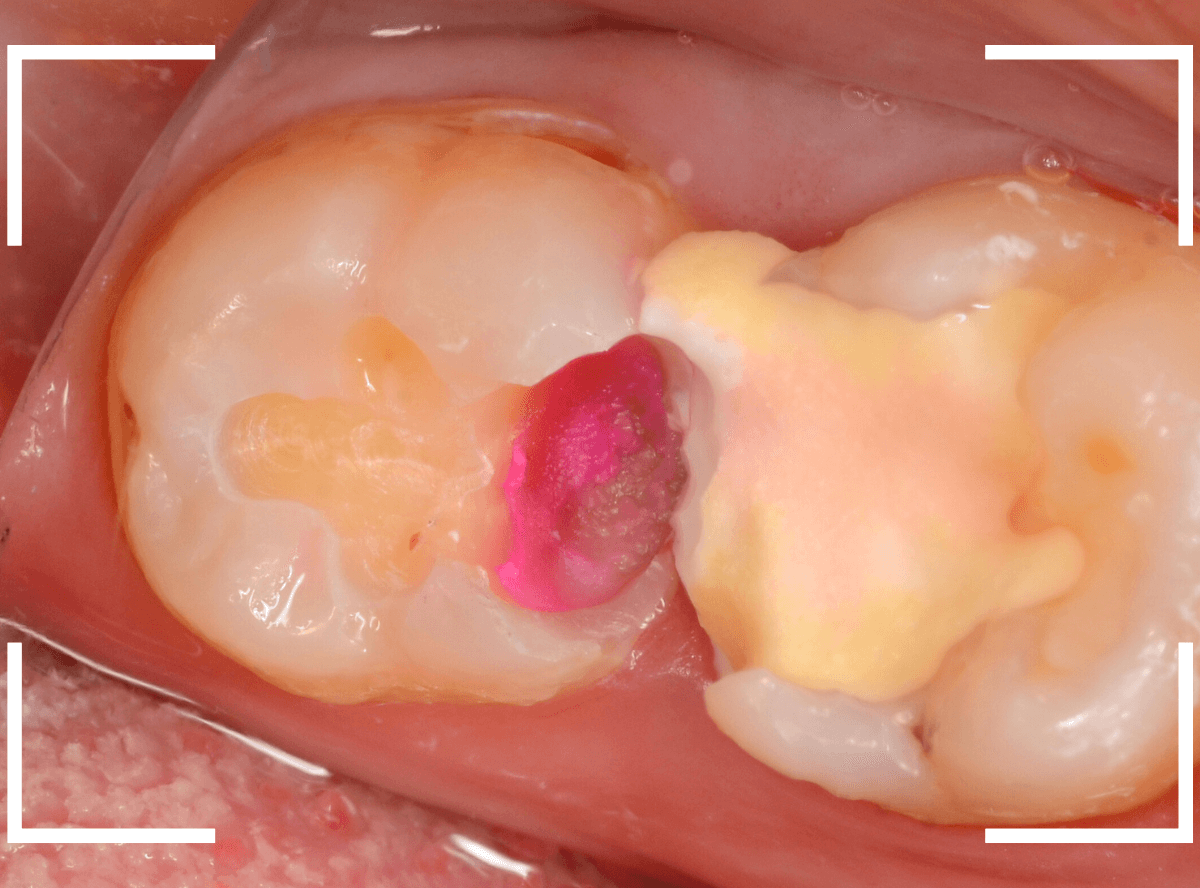

Case.22 痛みはないけど、歯のすきまから大きな虫歯

上の小臼歯の間が虫歯になっていた患者さんです。

症状はありませんし、見た目からも虫歯があるかはわかりませんでした。

レントゲン写真で確認します。

赤い線が虫歯、青い線が歯の神経です。

歯のすきまから両側に虫歯が大きく広がっているのが確認できます。

治療を開始します。

少し削ると、中からすぐに虫歯が出てきました。

ある程度、虫歯を除去したところで、う蝕検知液で確認します。

赤く染まっている部分が虫歯です。

まだまだ虫歯が中で残っている状況で、かなり深い虫歯なのが確認できます。

全ての虫歯を除去しました。

レントゲン写真からある程度確認出来ましたが、歯の神経スレスレまで虫歯が進行していました。

ここまで虫歯が進行していても、全く症状を感じない事も多いです。

そして、ある時急に痛みを感じるのです。

虫歯は急に進行しません。

治療後の定期検診で確実に食い止めましょう。